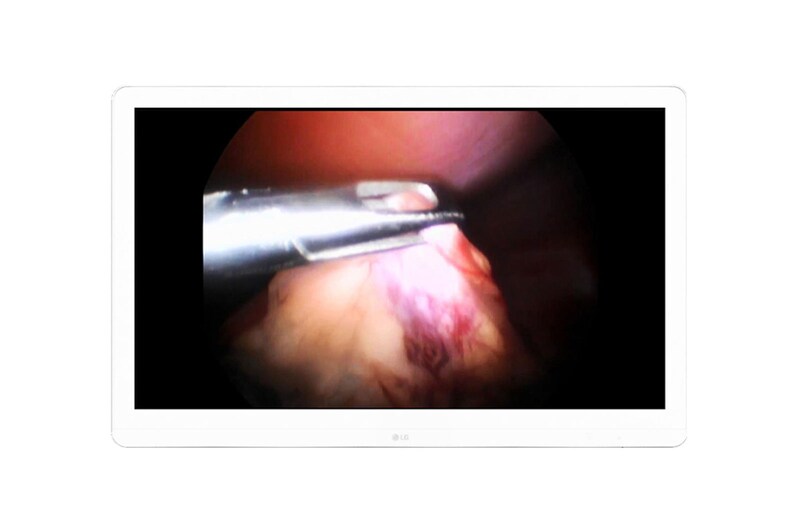

Monitor Quirúrgico 8MP